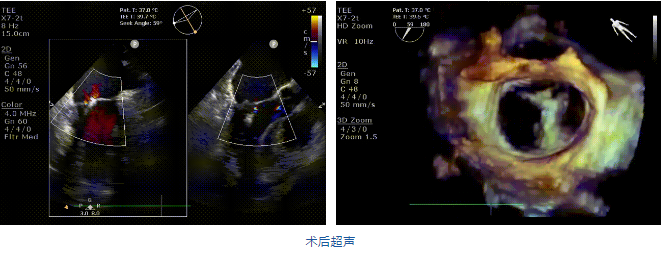

在阜外醫(yī)院潘湘斌教授團隊的支持下,手術(shù)經(jīng)股靜脈-房間隔入路,采用全身麻醉插管,在TEE和DSA引導(dǎo)下完成房間隔穿刺。置入JensClip瓣膜夾系統(tǒng)后,在左房調(diào)整瓣膜夾的位置和軸向,后進(jìn)入左室,在TEE引導(dǎo)下捕捉二尖瓣前后瓣葉,并關(guān)閉瓣膜夾。經(jīng)TEE反復(fù)確認(rèn)手術(shù)效果后最終鎖定并釋放瓣膜夾。術(shù)后即刻超聲顯示瓣膜夾位置穩(wěn)定,功能良好,二尖瓣反流由術(shù)前4+減少至微量,手術(shù)圓滿成功。